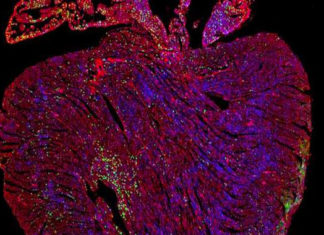

Científicos descubren cómo una mutación genética causa el autismo

Aunque investigaciones previas han asociado numerosas mutaciones genéticas con el autismo, pero no son claras cómo estas mutaciones contribuyen al desarrollo del autismo. Ahora, un...